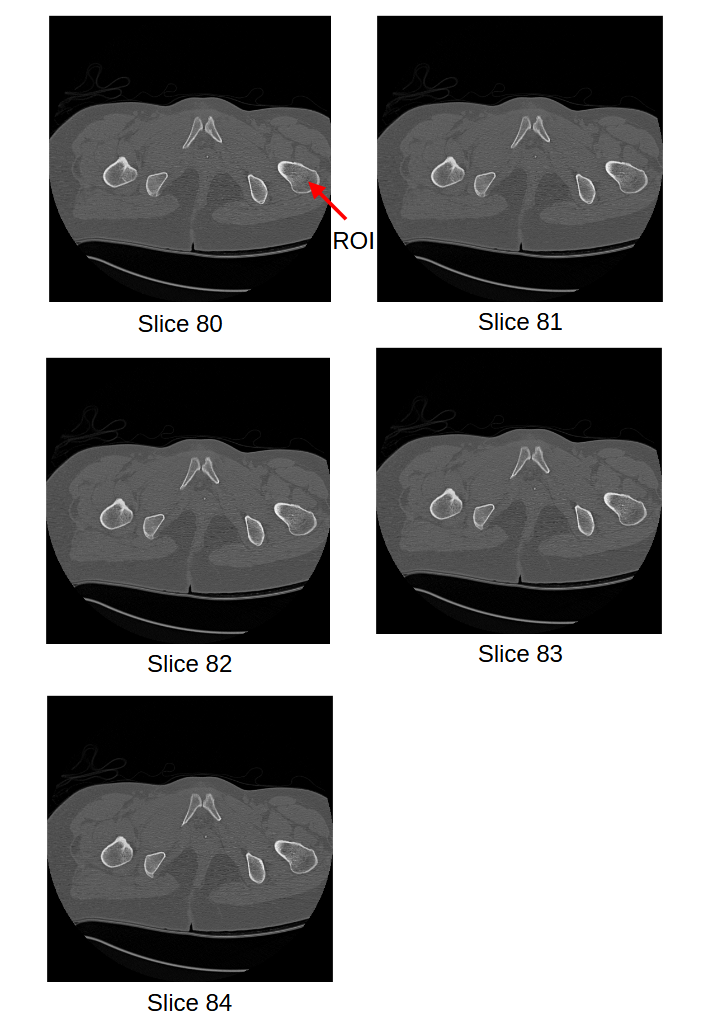

CT images assist the clinical practitioners to assesses the internal structure for deformity when met with serious injuries. CT images captures the intensity variations of different internal body parts like bones, muscles, fat, organs and blood vessels relative to the water in Hounsfield Unit [19]. The HU are mapped linearly to the gray scale range [0, 255]. CT Scanning captures human body in incremental scanning and provides up to 350 slices depending on the thickness of the slice or resolution of the CT scanning machine. The practicing clinicians needs to analyze each slice manually to precisely locate the deformity or injury in the internal structure. Manually analyzing slice-by-slice is a tedious task and the 3D structure need to be constructed in his imagination based on his learning and experience. Most important internal organ that will be assessed in all these CT slices is bone. Segmenting the bone in all these slices and reconstructing the 3D Structure will assist the clinicians in saving time and enough room for other medical procedures. Sample CT scan images [22] of pelvic bone from slice 80 to 84 with region of interest Pelvic bone femoral body is shown in Figure 2.

Refer to caption

Figure 2: CT Images Slices 80-84 with Region of Interest

After the traditional work flow, segmentation of the internal structure is performed on each slice of region of interest. To perform the task of image segmentation, each slice of CT Image is subjected to thresholding and followed by morphological operations, the boundaries of ROI are extracted. The results of segmentation on slice 80 to slice 84 are shown in Figure 3 for a threshold value above 400.

Figure 3: Contours of ROI